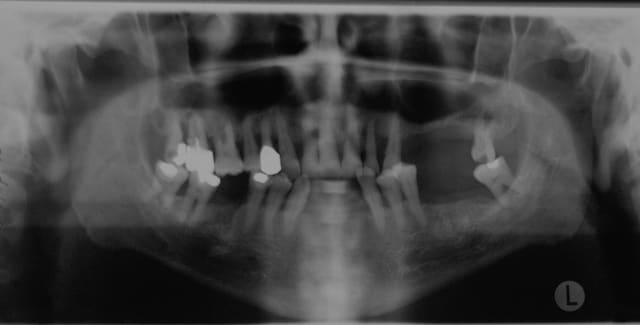

Joli boulot, la question que je me pose, c'est qu'il me semble voir sur la pano un pêche sur 25 et 27.

Est-ce que ça ne risque pas de foutre la greffe en l'air?

Joli boulot, la question que je me pose, c'est qu'il me semble voir sur la pano une pêche sur 25 et 27.

Est-ce que ça ne risque pas de foutre la greffe en l'air? »

Bien vu Fred ça m’interpelle aussi.

Si tu sais gérer les problèmes je te joins le pano de mon premier comblement de sinus (comblent mais pas soulevé) avec du TCP mélange à de la crête iliaque.